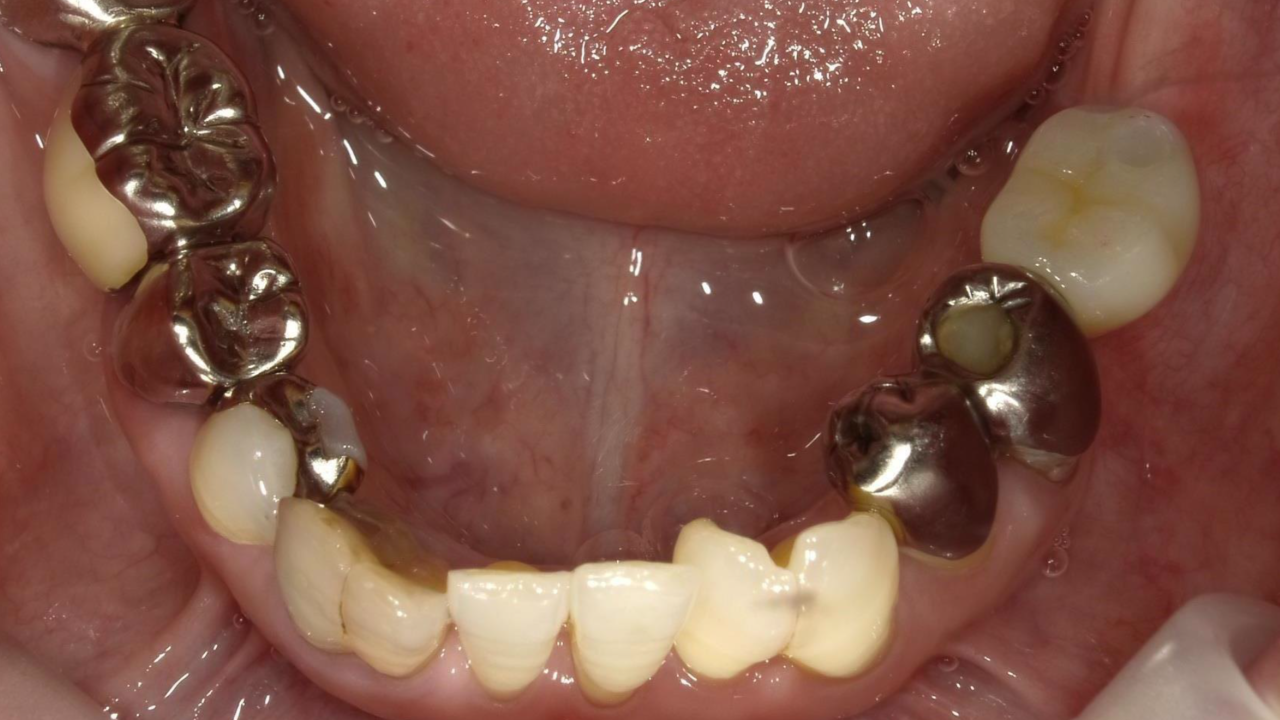

N・H様 女性 70代

Before

After

右下奥歯が噛むと痛くなり、来院されました。レントゲンで歯の根が破折しており、抜歯となりました。抜歯後にインプラント治療を希望され治療を開始。治療後、違和感もなく奥歯で何でも食べれるようになったと満足されていました。

治療期間・回数:11か月、18回

治療の価格:インプラント治療  550,000円 (上部構造含む)

治療のリスクや副作用:手術後に、痛みや腫れ、出血、合併症などを引き起こす可能性があります。噛む感覚がご自身の歯と異なる場合があります。見た目がご自身の歯と異なる場合があります。手術後にメインテナンスを継続しないと、インプラントが脱落するリスクがあります。